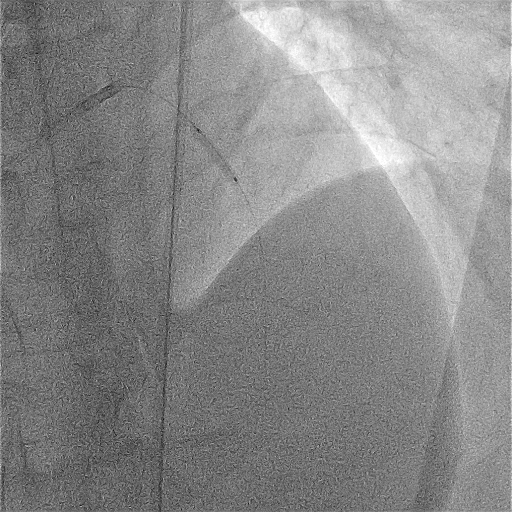

The patient arrived intubated with BP 110/62 mmHg and pulse 60/min. Echocardiography showed an LVEF of 30% with severe anterior wall hypokinesia. Coronary angiography revealed a right-dominant system with normal LMCA, LCX, and RCA (TIMI 3 flow). The proximal LAD demonstrated a subtotal thrombotic occlusion (95–99%) with a large thrombus burden and TIMI 1 flow.

01.avi

The patient arrived intubated and hemodynamically stable. Right femoral artery access was obtained with a 7 Fr sheath. Diagnostic angiography confirmed subtotal thrombotic occlusion of the proximal LAD with TIMI 1 flow and a large thrombus burden. PCI was initiated using a 7 Fr EBU 3.5 guiding catheter and a Sion guidewire. An ELIMINATE 7 Fr aspiration catheter was advanced, and multiple aspiration passes were performed, but significant residual thrombus persisted with high risk of no-reflow.